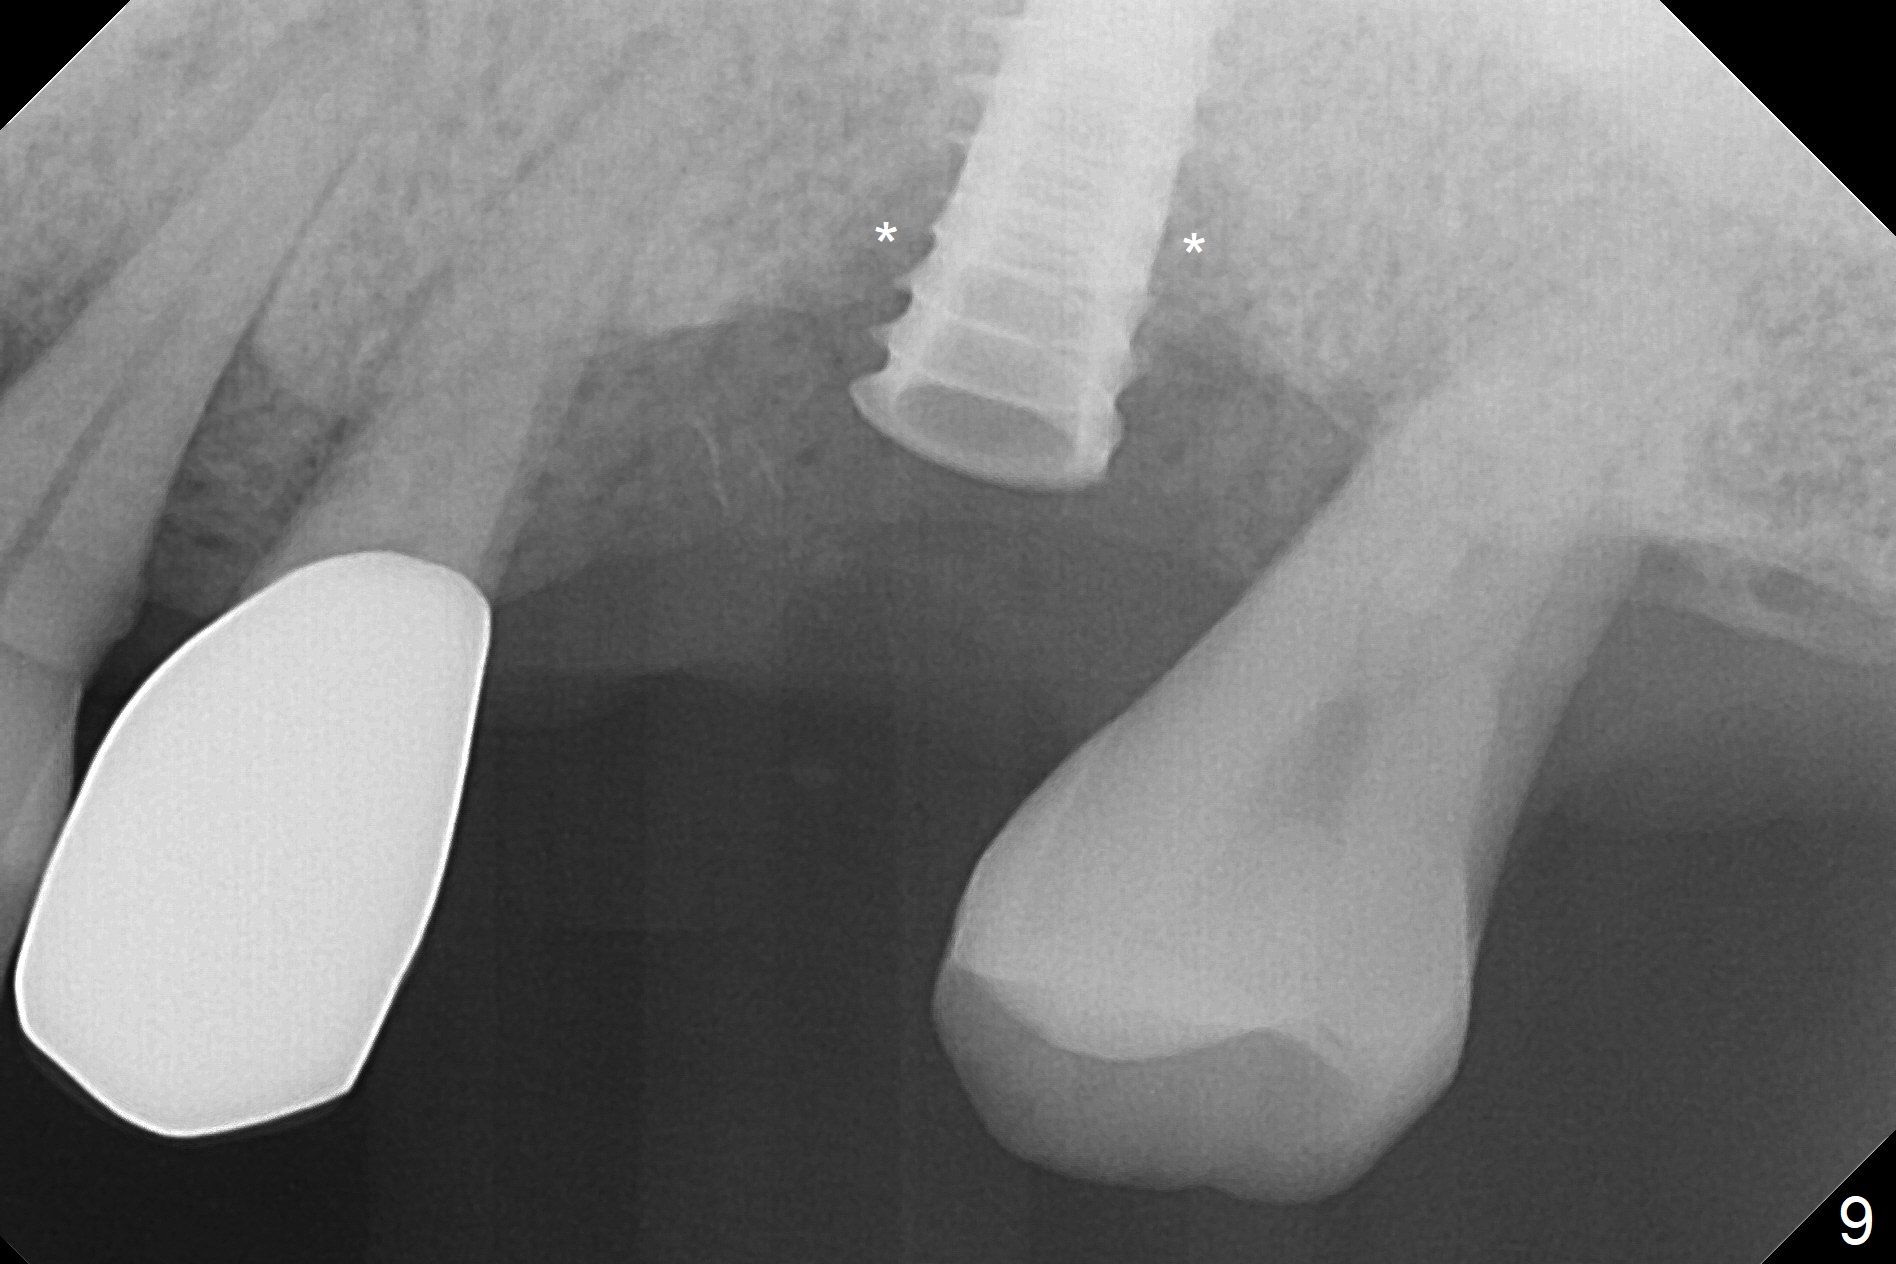

The amount of the bone graft mesial and distal the implant seems to reduce 3 and 4 months postop, respectively (Fig.6,7 arrowheads). When the acrylic is cut off 4 months postop, the bone graft is loose. The gingiva is unhealthy. The abutment and implant are loose. A healing abutment is placed (5x4 mm). The implant is torqued to 35 Ncm 6 months postop with the healing abutment reapplied. The patient will return for follow up nearly 9 months postop. A larger healing abutment will be used if the implant is stable. Two weeks later, use a smaller restorative abutment for easy impression. In fact the implant is unstable with #15 mesial shift due to abnormal occlusion with #17 (Fig.8). Bone density around the implant is low (* in Fig.9 (PA), 10,11 (CT sagittal, coronal sections)). A healing screw is placed for self healing. A 2nd option is to remove the implant (Fig.12), BEB (Fig.13) and place the implant deeper (Fig.14) or larger one (5.5-6.5x13 mm). The 3rd option is to place larger and longer implants (Fig.15 (tapered), 16 (cylindrical)). The implant access has partially closed 14 months postop, but there is a small buccal opening with sanguine exudate. Incision reveals severe bone loss around the implant; the mobile tooth #15 is extracted (Fig.17). After debridement and irrigation with normal saline, Vera Graft (Fig.18 *) and Collagen plug are placed with periodontal dressing.